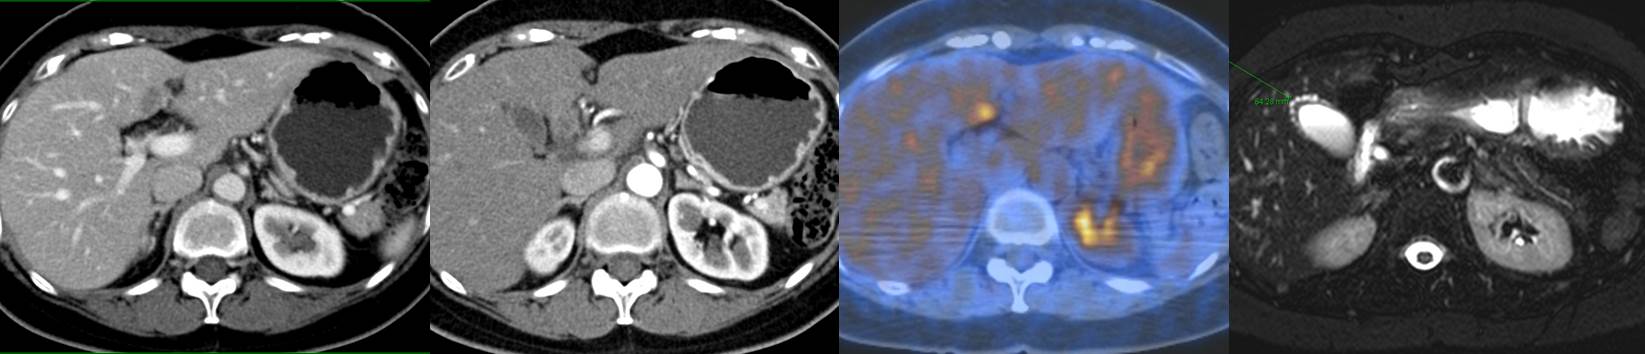

Áõ·Ê 3. F/60. ¹«Áõ»ó. Ÿ¿ø °ËÁø ÃÊÀ½ÆÄ¿¡¼­ ƯÀÌ¼Ò°ß ¾ø¾úÀ¸³ª CA 19-9 310 U/mL ¹ß°ß. ÀÇ·Ú ÈÄ Àç°Ë¿¡¼­ CA 19-9 677.3 U/mL ¼Ò°ßÀ̾ú°í CT¿Í PET¿¡¼­ liver segment S4ÀÇ ÀÌ»ó ¼Ò°ßÀ¸·Î ¼ö¼ú. ¼ö¼ú ÈÄ CA 19-9 Á¤»óÈ­ µÇ¾úÀ½.

Liver and gallbladder, left hemihepatectomy and cholecystectomy :

1) Eosinophilic abscess, S4, liver 1) size: 1.8x1.2 cm 2) palisading granulomas 3) negative resection margin

2) Consistent with adenomyoma, gallbladder